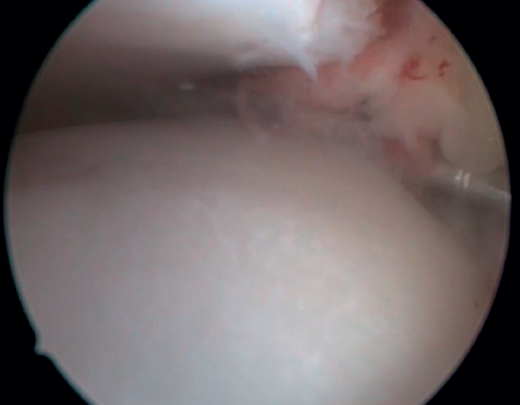

Bony AAI due to osteophytes has also been linked to the presence of chronic instability. It has been postulated that altered joint kinematics secondary to ligament insufficiency favors the development of osteophytes in the anterior region of the tibia and talus(36,37). Recent studies have questioned the theory of repeated capsular traction as the origin of osteophytes in sports(38), as it is easily demonstrated that osteophytes are located intra-articular within the capsular insertion, in the context of ankle arthroscopy (Figure 2). Therefore, ankle dorsiflexion arthroscopy is essential to safely resect osteophytes without damage to the capsule or overlying structures, whereas the classical traction technique (invasive or otherwise) would make resection extremely difficult, and is thus not recommended nowadays for routine use(3,39). Vega distinguished between two types of osteophytes(3), according to whether they are caused by repetitive trauma (peak-shaped) or instability (visor-shaped). The concept of micro-instability is associated with repetitive micro-trauma, which could be the origin of osteophytes with this characteristic morphology (Figure 3).

The confirmation of AAI is made by direct vision during arthroscopic examination (Figure 4). This technique allows us to visualise the entire joint, assess the state of the articular cartilage and ligaments, detect the presence of capsular adhesions, synovitis, synovial thickening, loose bodies, etc. It also allows us to carry out functional tests to reveal possible associated instabilities or to assess how the soft tissues causing pain suffer impingement. In our experience, the presence of ATFL lesions is very frequent.